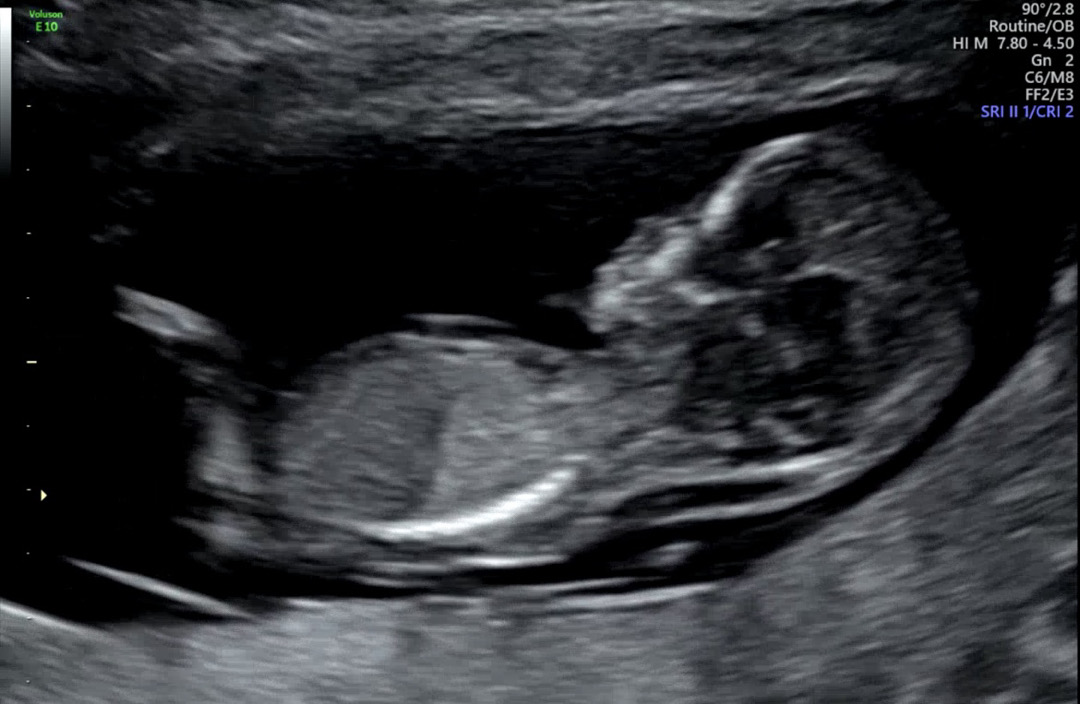

12주 3일인데 각도법 성별 궁금합니다😆

딸인거같아요!